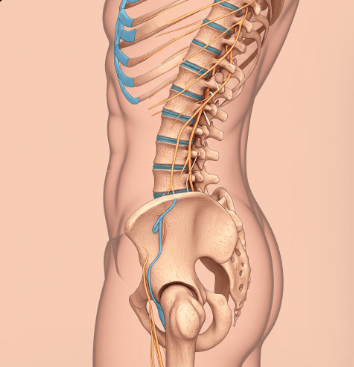

척추 협착증이란?

척추 협착증은 척추 내부의 신경이 지나가는 통로가 좁아져서 신경을 압박하는 질환이에요.

마치 수도관이 녹이 슬어 좁아지듯이, 척추관이 좁아지면서 그 안의 신경과 혈관을 눌러 통증을 유발하는 거죠.

📊 발생 위치

요추(허리): 전체 환자의 약 80% 차지

경추(목): 약 15% 발생

흉추(등): 드물게 발생